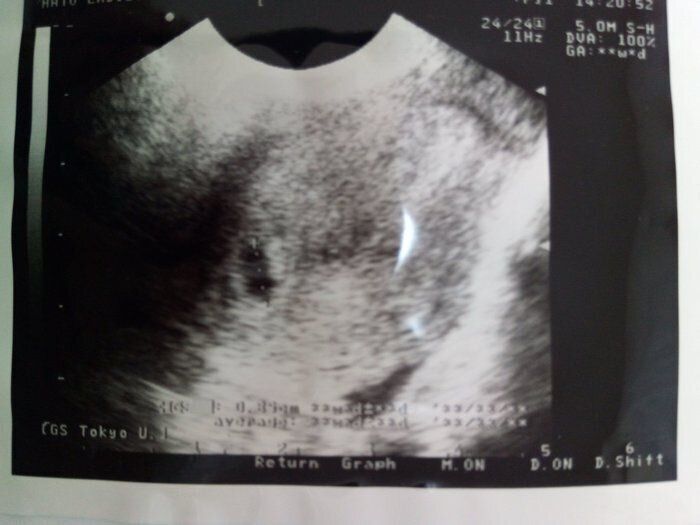

ママにエールさんの妊娠6週目のエコー写真

薄茶色のおりもの(出血)があり、気になって産院へ電話。「とりあえず、診察へ」と言われて受診しましたが、妊娠初期によくある程度の出血だから大丈夫とのこと。出血止めの薬だけ処方されました。ちょうどこの時、エコーで白い小さな粒を確認。「これが赤ちゃんに成長していきます」と先生に聞いて、愛しさでエコー写真をしばらく眺めていました。夫に見せたら、「ちっこい」と笑っていました。